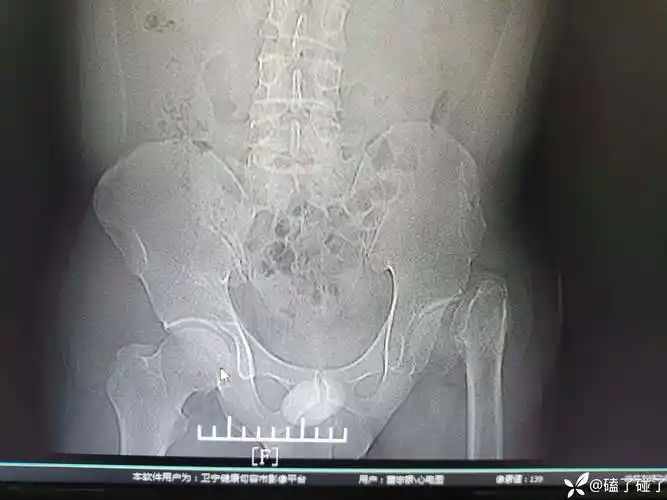

髋臼骨折篇

髋臼骨折

髋臼骨折一例

左侧髂骨粉碎性骨折一例,请各位看看! - 骨科专业讨论版 -丁香园论坛

病历分享|30岁男性陈旧性髋关节骨折,望各位老师提供建议

陈旧髋臼骨折全髋,3d